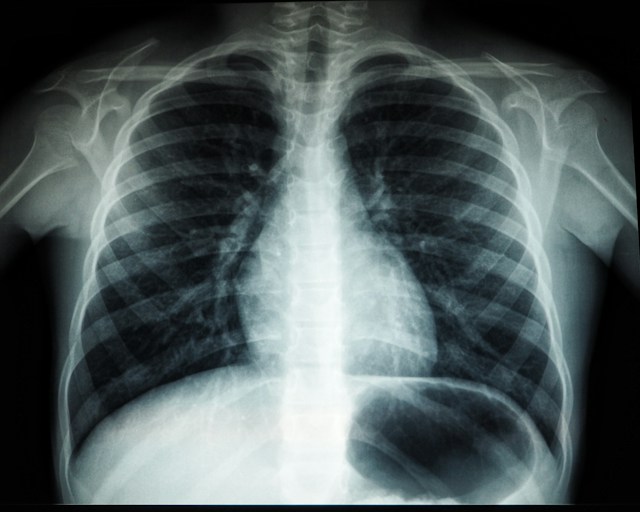

Forcément un climat économique aussi favorable n’est pas le fruit du hasard. Selon le rapport de Xerfi : « les efforts de rattrapage en équipements lourds (IRM, scanners, TEP) déjà engagés » sont l’une des raisons à mettre en avant.

Enfin, une troisième raisons est à mettre en lumière selon le cabinet d’études. « Les groupes hexagonaux sont particulièrement bien positionnés sur les segments des radiopharmaceutiques et des produits de contraste… La tendance est également positive pour les acteurs du traitement et de l’analyse des images, qui profitent de la montée en puissance de la médecine personnalisée en cancérologie. Ainsi, IntraSense, spécialiste des solutions d’imagerie médicale pour les maladies chroniques et l’oncologie, dispose désormais de près de 1 000 sites installés, dont la moitié en France ».